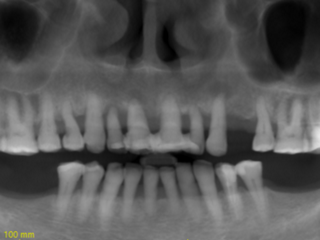

Guided FP1 maxillary rehabilitation with Straumann® STARconcept™ and Straumann iGuide™. A clinical case report by Dr. David Norré, Belgium.

Facially driven Smilecloud design with a focus on preserving tissue and bone. Planned in Smile in a Box and executed with the iGuide protocol; shared pin positions align the drill and prosthetic guides for chairside pickup of the pre-designed provisional. Day-5 follow-up shows the screw-retained provisional in place.

• Pre-operative panoramic X-ray.